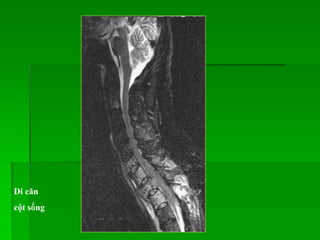

Di căn

• 4 dạng di căn cột sống:

- Hủy xương khu trú: tín hiệu thấp trên T1W, T2W

- Xơ xương khu trú: tín hiệu thấp trên T1W, T2W

- Tổn thương không đồng nhất, lan tỏa: tín hiệu thấp trên T1W, T2W

- Tổn thương đồng nhất, lan tỏa: tín hiệu thấp trên T1W, T2W

• Mức độ bắt Gd thay đổi.

Di căn thân sống và tủy sống

cột sống